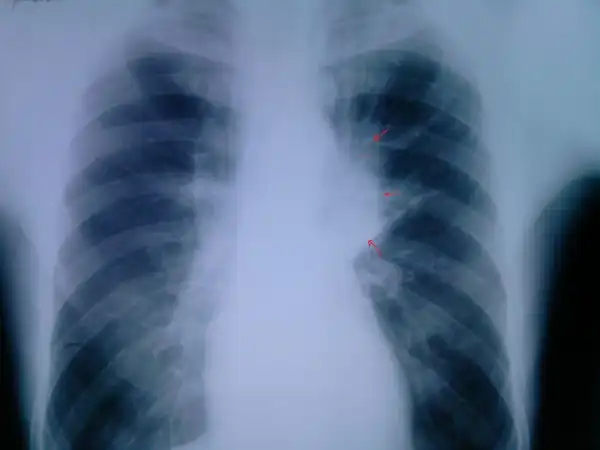

Пациент №2:

Флюорограмма:

Пациенты 6 и 7 тоже под вопросом... Не четкая картина.